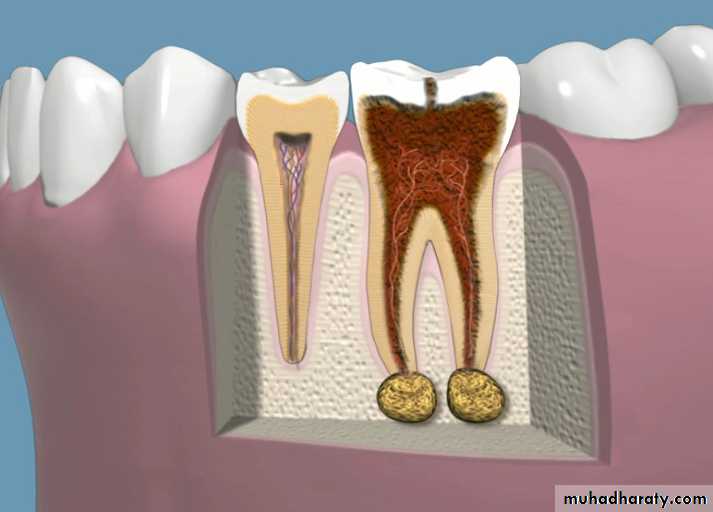

Apical PeriodontitisIs the inflammation of the periodontal ligament around the root apex.

There may be resorption of the periapical bone and sometimes the root apex.

A mass of chronically inflamed granulation tissue at the apex of a nonvital tooth.

Most lesions are discovered on routine radiographic examination.A well-defined radiolucency of bone apical to the offending tooth. Loss of the apical lamina dura.

The lesion may be circumscribed or ill defined.

The size is variable.